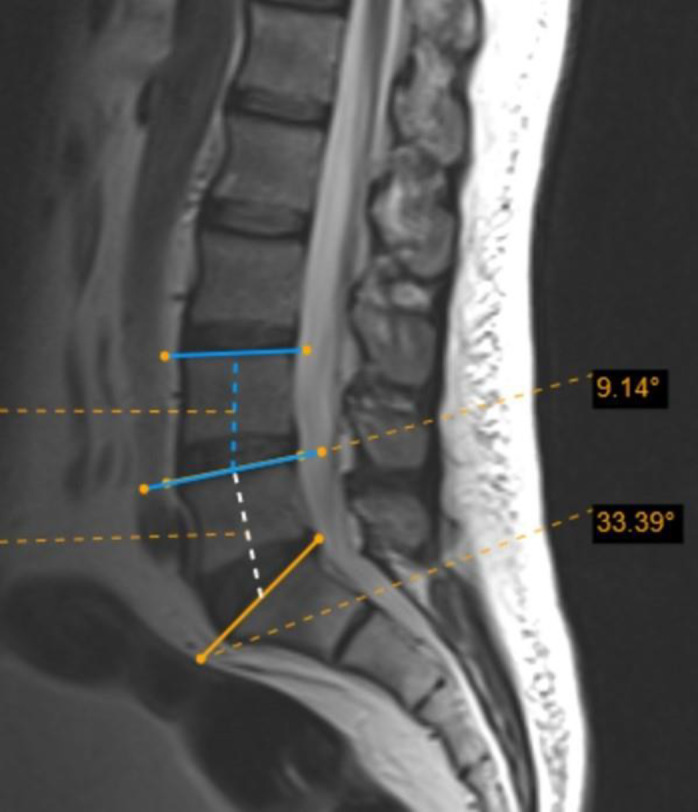

Methods: We recruited 220 patients referring to our hospital for routine lumbar MRI during 2020-2021. All the participants were subject to routine sagittal lumbar MRI, whole spine localizer scan, and coronal MRI to numerate lumbar vertebrae. Five vertebral angles (A, B, C, D, and delta) and dehydration in L4-L5 and L5-S1 discs were assessed in sagittal MRI scans. Data were analyzed using SPSS 26.

Results: Out of 220 participants (mean age: 44.29 ± 14.14 years), 36 (16.36%) were diagnosed with LSTV. Among those diagnosed with LSTV, L5-S1 dehydration was less frequently observed compared to other participants (P < 0.001). Multivariate regression showed that dehydrated L4-L5 disc, non-dehydrated L5-S1 disc, increased A-angle, and decreased D-angle can independently predict LSTV. The median A-angle was significantly larger in LSTV patients than in non-LSTV participants (P = 0.038), while the medians of C-angle, D-angle, and delta-angle were significantly smaller in the LSTV group (P < 0.05). A C-angle ≤ 35.5˚ could diagnose LSTV with sensitivity and specificity of 72.2% and 57.6%, respectively. A delta angle ≤ 8.5˚ could diagnose type 2 LSTV with 92.3% sensitivity and 87.9% specificity.